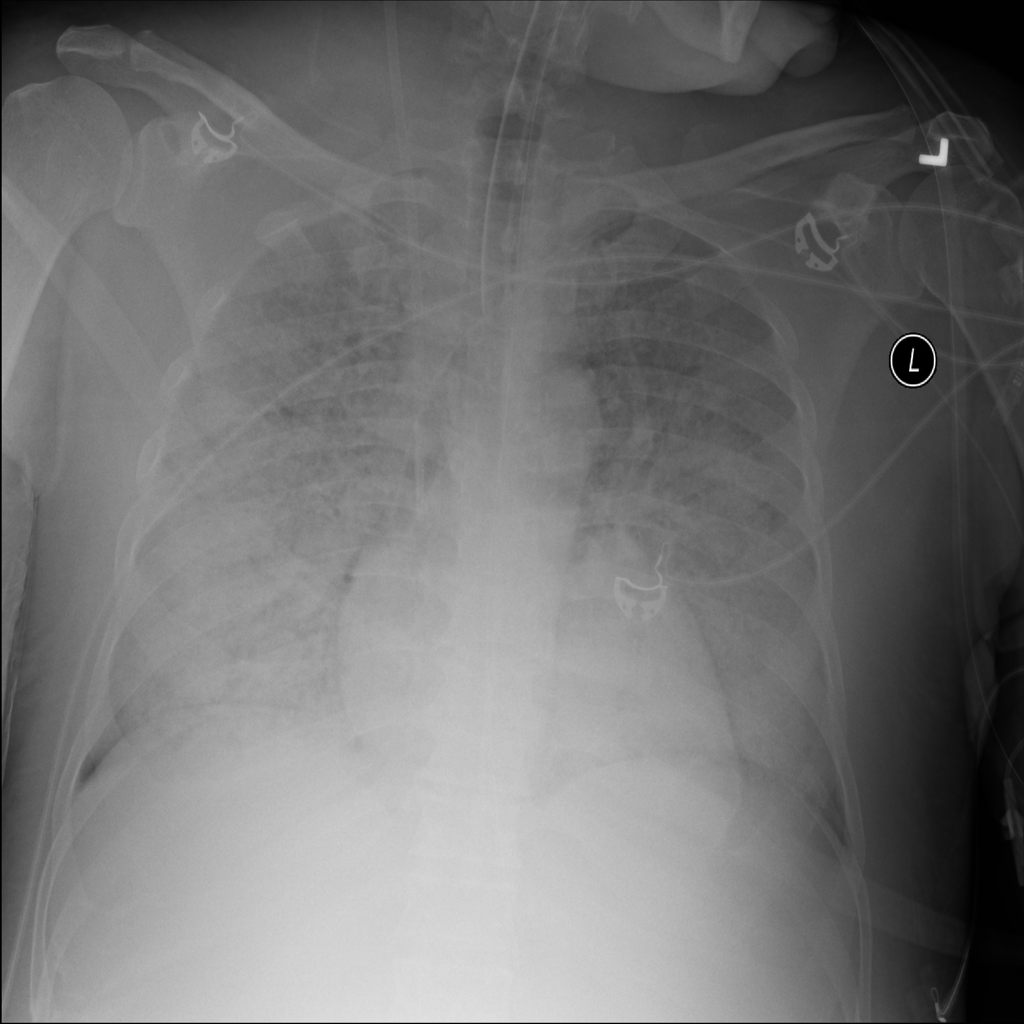

PAT-E828 · IMG-005Edema

PAT-E828 · IMG-005

AP